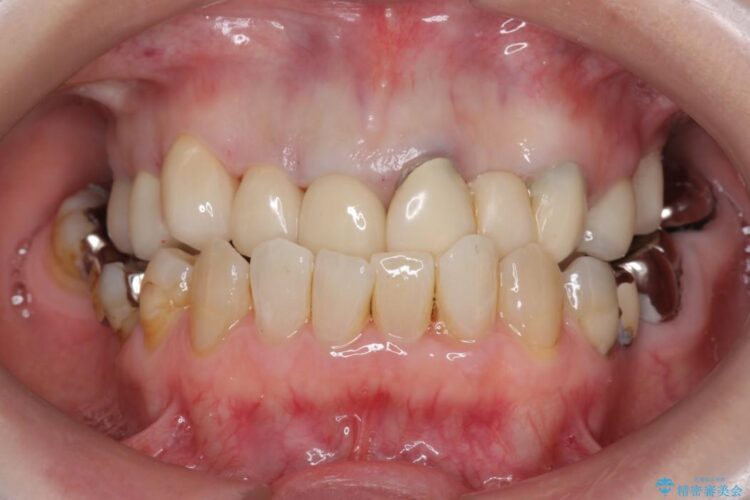

前歯のかぶせ物に関しましては、内面が金属で覆われているため歯茎にその色が透けて見えるという審美的な問題と、かぶせ物と歯の境界が不適合であるという問題がありました。

今回の症例では金属の色が透けていることを気にされていたので、土台から金属を除去し、金属を使用していないオールセラミックのかぶせ物を使用することとしました。